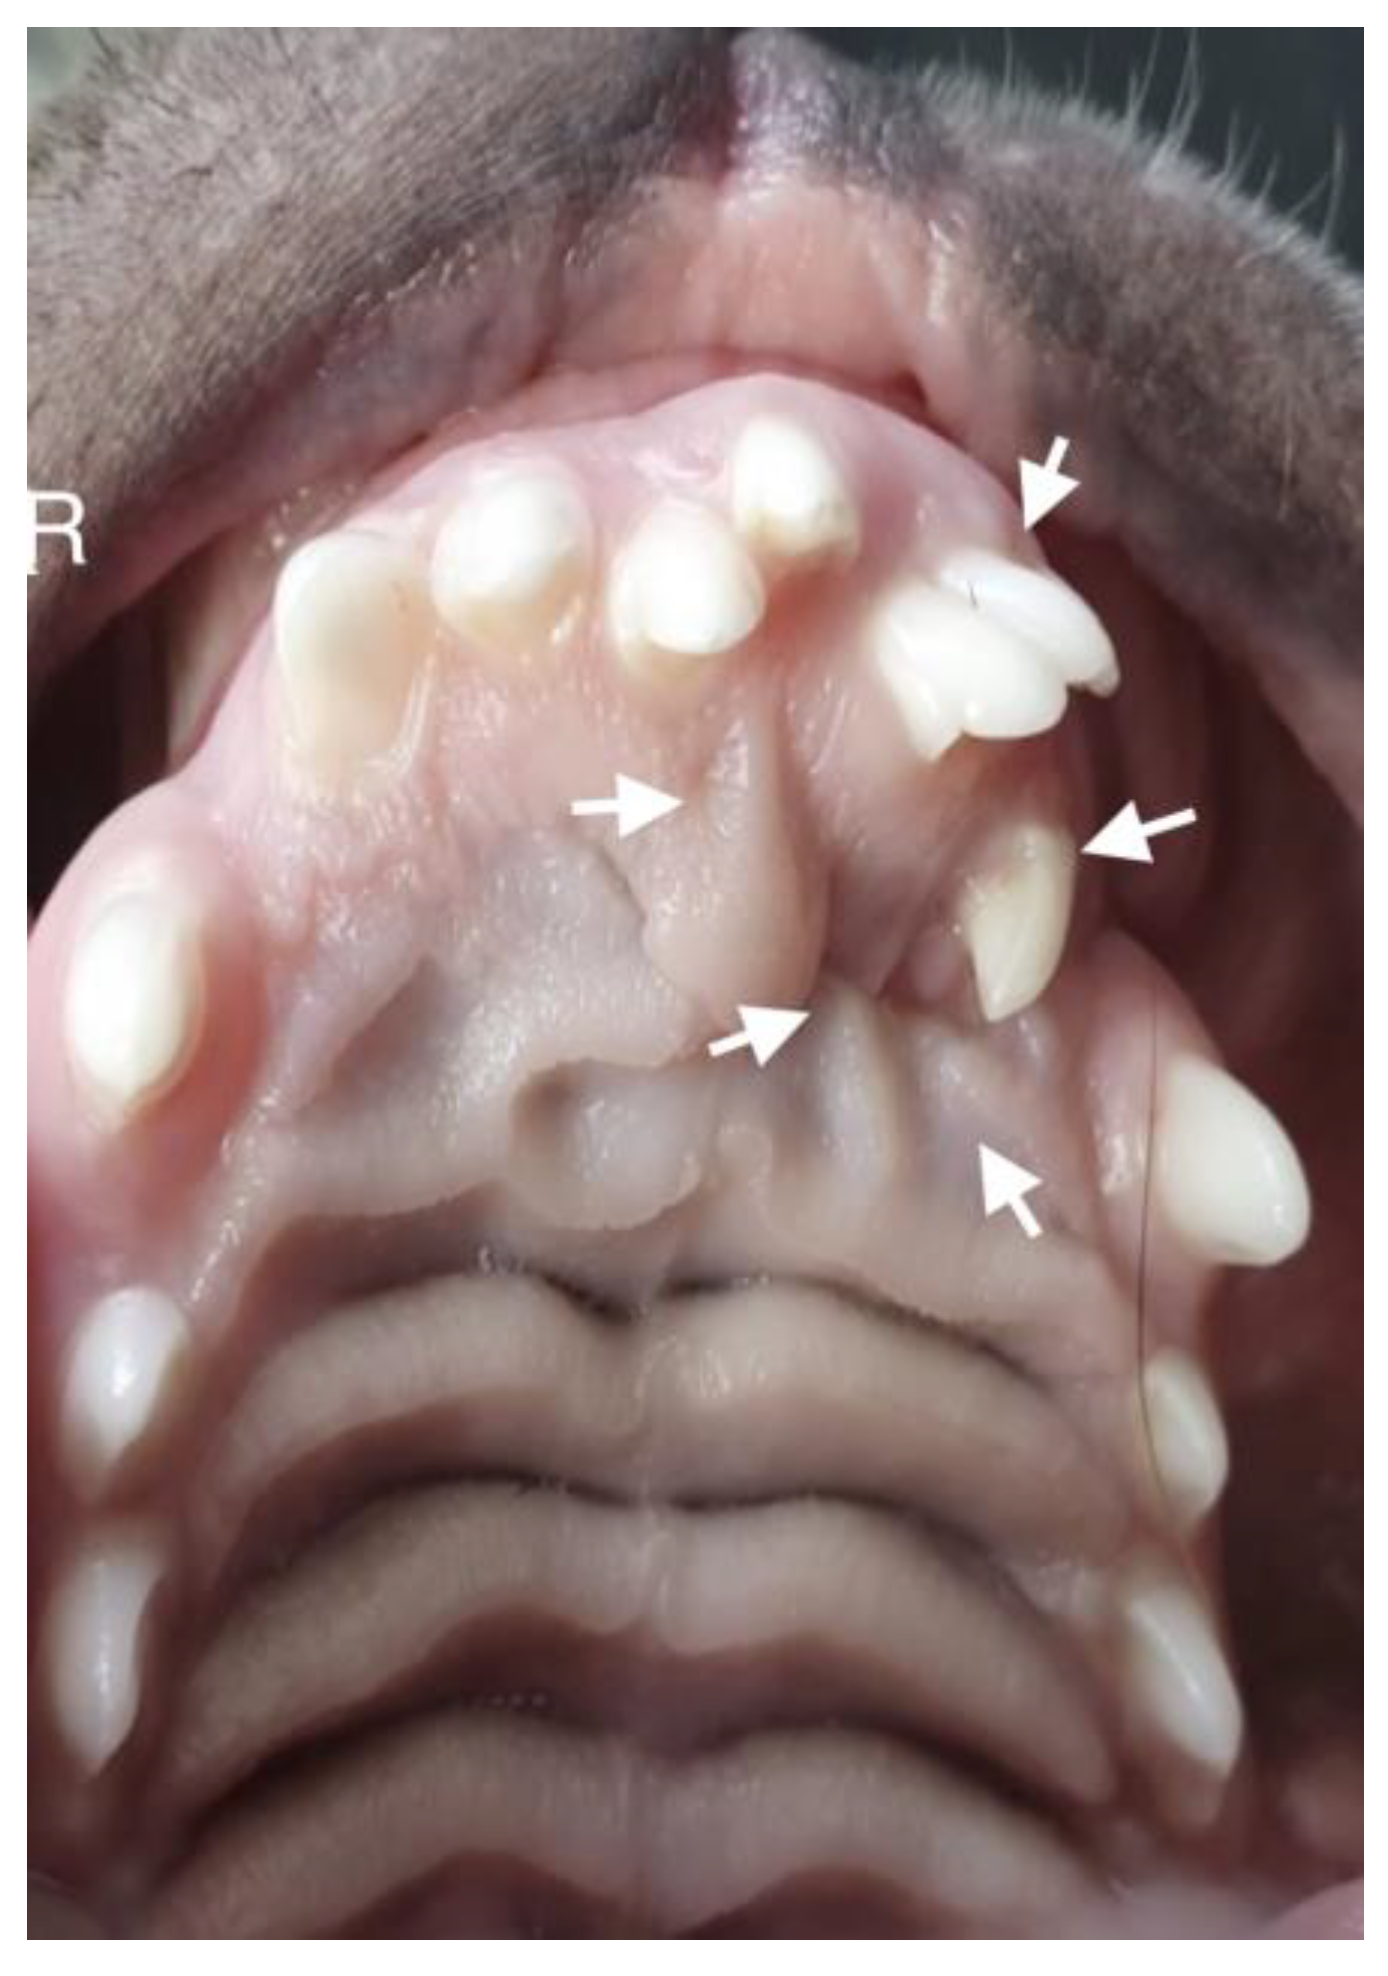

A 10-month-old American Staffordshire Terrier dog was referred for an orthodontic consultation due to abnormal alignment of the maxillary teeth and the resulting bite injuries. Clinical examination revealed three properly aligned incisors on the right side and four incisors (including one tooth with a double crown) on the left side arranged chaotically (Figure 7). Intraoral examination revealed an abnormal palatal crease in the projection of teeth 103–203 and a hard and painful protrusion about 3 cm in diameter on the left side. The roentgenogram showed the presence of three additional incisors, including two unerupted ones, growing in the opposite direction to the alveolar process. The double tooth on the X-ray appeared to be a fused tooth (tooth fusion occurs as a result of physical force or pressure on an adjacent tooth’s bud, leading to the contact of the two tooth buds and their fusion before calcification) [12]. The abnormal growth of the incisors on the left side caused pressure on the incisal bone, along with skewing of the nasal septum to the right side (Figure 8). The third incisor, along with an additional third incisor, showed radiographic features of a dentigerous cyst. A decision was made to perform open extraction of the ectopic teeth using the CLP method.

Figure 7. On the left side, the teeth with abnormal eruption are marked with arrows on the X-ray. The right radiograph shows the status 28 days after surgery. Properly formed bone tissue can be seen, with no signs of inflammation or alveolar bone atrophy (marked with arrows).